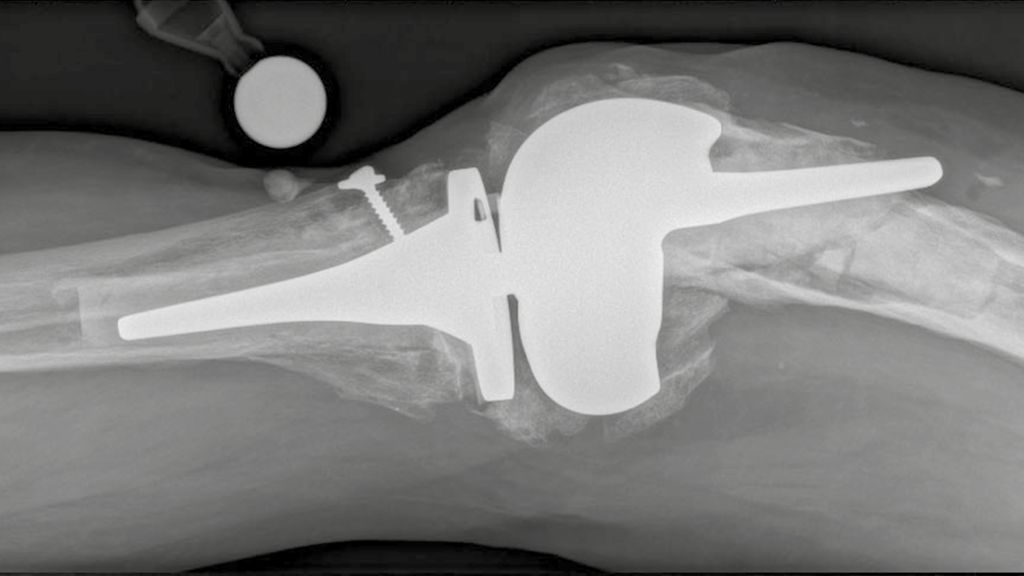

Knorpeldefekte im Knie können die Lebensqualität einschränken und langfristig zu Arthrose und der Notwendigkeit eines Gelenkersatzes führen. Es gibt diverse Behandlungstechniken, aber ...

Luxationen des Kniegelenks sind sehr seltene, aber schwerwiegende Verletzungen, die häufig mit Komplikationen einhergehen und unbehandelt zu schweren Instabilitäten im Knie führen können ...